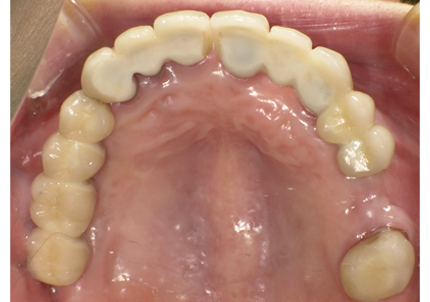

10.上顎補綴物装着(2008年12月)

12.上顎補綴物装着(2009年5月)

22.上顎左側6番補綴物装着(2021年10月23日)